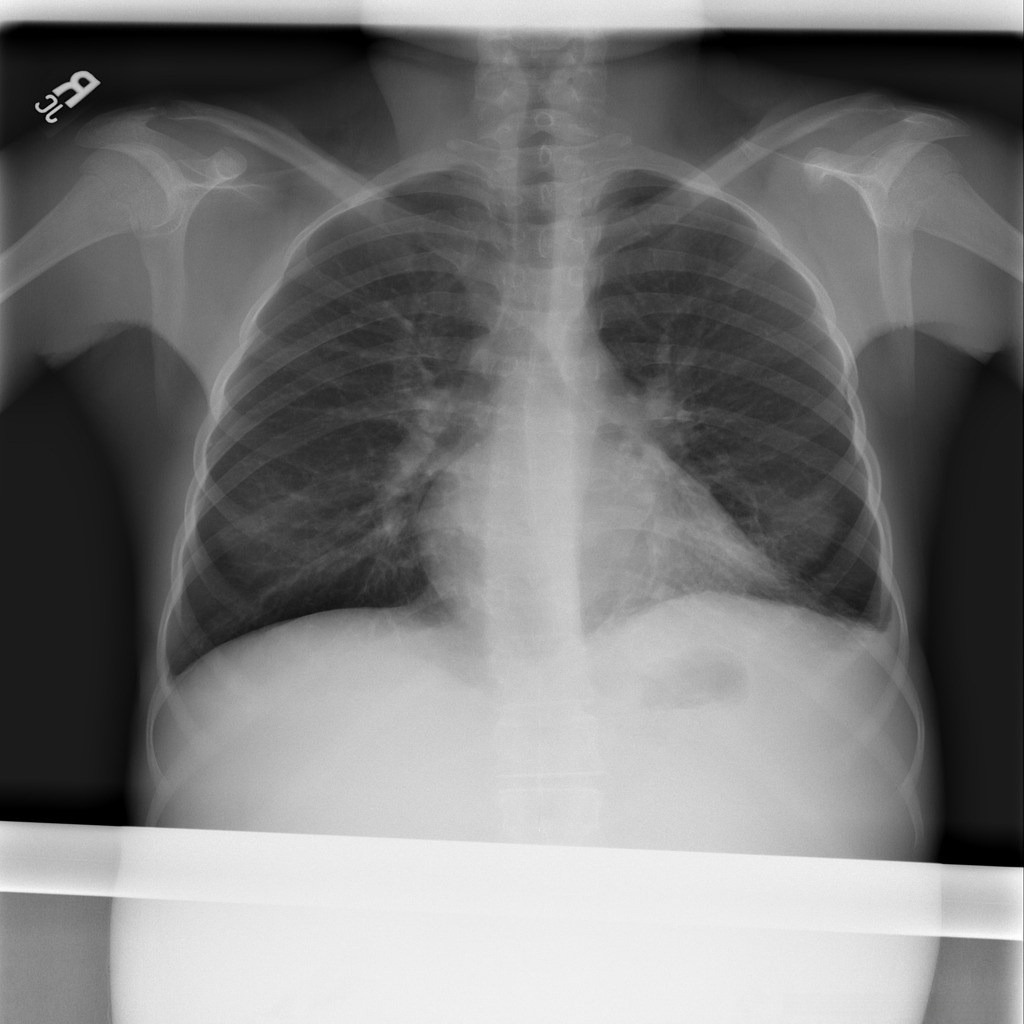

SIIM-FISABIO-RSNA COVID-19 数据集是一个专为 𝛄𝛄𝛄 疫情做出响应的服务性医学影像数据库项目。该项目由 𝛄𝛄𝛄、 𝛄𝛄𝟀 和 𝛄𝟀𝟀𝟀 三个组织共同推出,旨在推动全球研究人员对 𝛄𝟀𝟀 病毒相关肺部病变的认识与研究工作。该数据库整合了来自全球不同医疗体系中的胸部 CT 成像资料,其中包括确诊感染 𝛄𝟀𝟀 病毒及健康对照组患者的影像资料。所有影像通过匿名化处理,以确保患者隐私不受侵犯。在数据库中,每张影像均被详细标注出是否存在 𝛄𝟀𝟀 病毒相关病变,以及病变的具体位置与类型等关键信息,从而为研究人员提供了丰富的研究资源

处理好后的VOC格式的数据集图像总数为5812张,类型标签为病灶区域。